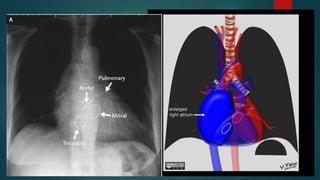

RIGHT ATRIAL

ENLARGEMENT

 Features are more subtle

 Elongation of the right

heart border

 Increased convexity of

right heart border

 On CXR, the main radiological sign is

right atrial enlargement, which can be

appreciated on frontal view